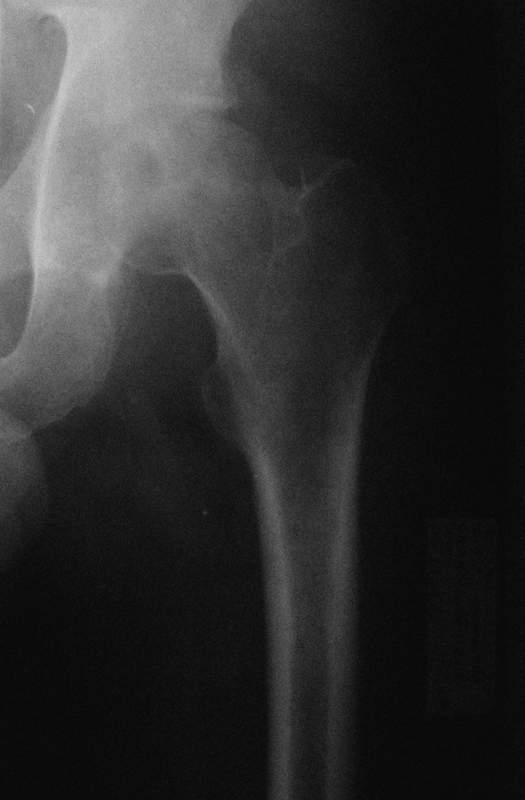

Молодой человек, 37л. Начало заболевания сентябрь 2007, резкие боли в области лев. тазобедренного сустава, повышение температуры до 39 гр., в течение недели, лабораторные данные: лейкоцитоз со сдвигом влево. Посев крови на стерильность возбудителя не выявил. По данным Рг, РКТ выставлен диагноз: Левосторонний коксит? Асептический некроз? Проводилось лечение: цефсон в/в неделю, иммобилизация кокситной повязкой 1 мес. Обратился повторно 10 дней назад с жалобами на сильные боли в левом тазобедренном суставе, белая кровь – нормограмма, СОЭ 46 мм/ч. На сегодняшний день: болей не отмечает. Лаб.данные: белая кровь – нормограмма, СОЭ 30 мм/ч. Рентген и РКТ прилагаем.

Мне представляется, что предоставлен случай аваскулярного некроза головки бедра. Для определения тактики лечения необходимо выполнить ренгенограммы лучшего качества и посмотреть все срезы на уровне головки. Предоставленные срезы -уровень ямки,т.е. малонагружаемой зоне, наличие в этой зоне участков сегментарного некроза скорее всего не приведет к деформации головки, при таком варианте разгрузка конечности на 3-4 мес может привести к благоприятному исходу.

При наличии участков некроза внутри головки близко к нагружаемой зоне для профилактики имперссионного прелома, вероятно, целесообразно выполнить Core Decompression (тема обсуждалась на форуме). В случае расположения участков некроза, затрагивающих суставную поверхность в нагружаемой зоне может быть целесообразным выполнение операций на проксимальном отделе бедра, ставящих целью выведение участков некроза из под нагрузки. Ну и протезирование, конечно, как вариант.